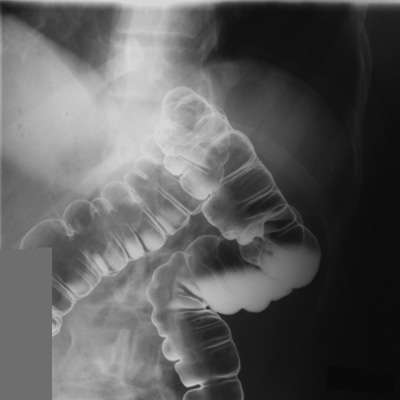

Take RPO and LPO spot images of the sigmoid colon.

Rotate the patient back into LPO position. Take spot image

of hepatic flexure.

- Rotate the patient into RPO position.

Take spot image of splenic flexure.